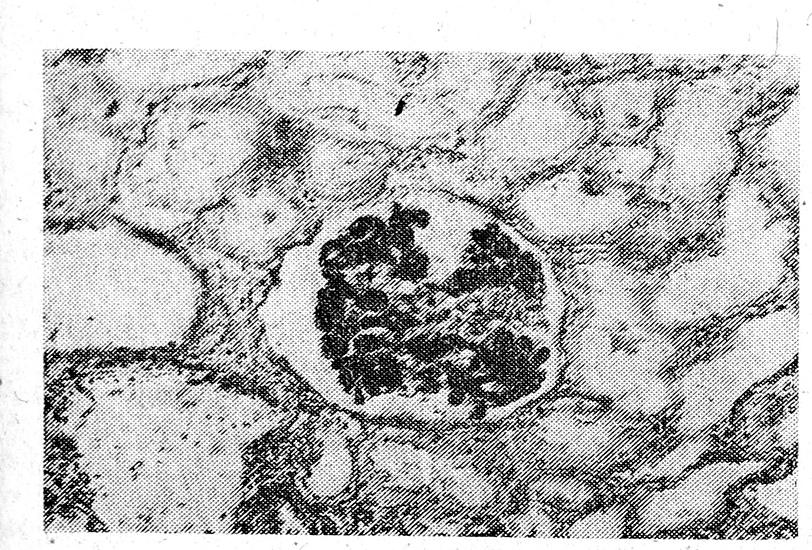

Результаты патогистологического исследования свидетельствовали о наличии комплекса расстройств гемодинамики во внутренних органах при черепно-мозговой травме. Следует отметить прежде всего выраженные признаки застойного полнокровия паренхиматозных органов, расширение просвета сосудов и заполнение их свободно расположенными эритроцитами. Однако гемоциркуляторные нарушения не ограничивались лишь признаками гиперемии. В различных отделах головного мозга, легких, печени и почек, в сосудах малого! калибра отчетливо прослеживались явления стаза и агрегации эритроцитов в виде хорошо известного сладж-феномена, реже имела место агглютинация с частичным гемолизом эритроцитов. Это могло сочетаться с транссудацией плазмы крови и выраженным периваскулярным отеком, что, как правило, наблюдалось в головном мозге. В венулах и венах легких на фоне диффузного геморрагического диатеза обнаруживались крупные агрегаты плотно упакованных эритроцитов, и одновременно с этим на внутренней поверхности сосудов в ряде случаев выявлялась положительная реакция на фибрин, что позволяло предположить наличие своеобразного феномена выстилания фибрином стенок сосудов [4а]. Однако обнаружение истинного тромбоза в микроциркуляторном русле изучаемых органов было сравнительно редким явлением. Исключение составляли лишь почки, в клубочковой капиллярной сети которых часто встречался плотно агрегированный фибрин, вызывающий полную окклюзию микроцирку ляторно го русла (рис. 1). Кроме того, в паренхиме почек постоянно обнаруживались и такие признаки ДВС-синдрома, как межуточная геморрагическая инфильтрация и некротические изменения в кортикальных отделах. В артериолах и венулах головного мозга на фоне диффузных кровоизлияний и экстравазатов, перицеллюлярного и периваскулярного отека в 'отдельных случаях имело место пристеночное расположение плотных гомогенных эозинофильных масс, дающих положительную реакцию на фибрин (рис. 2). Иногда эти массы, упакованные в гомогенные глобули, расценивались нами как гиалиновые тромбы, которые вызывали полную обтурацию микроциркуляторного русла. В то же время в сосудистых сплетениях желудочков мозга глобулярные белковые коагуляты встречались редко. В них, как и в синусоидах печени, в основном преобладало сгущение крови с образованием клеточных агрегатов. Следует также отметить, что прослеженные нарушения гемоциркуляции в различных органах нередко сочетались с выраженными изменениями самих сосудистых стенок в виде плазматического пропитывания и отека, а также набухания эндотелия.

Рис. 1. Фибриновые тромбы в капиллярах клубочка почки. Дистрофия и некроз эпителия почечных канальцев. Окраска по Маллори. Ок. 10, об. 20.